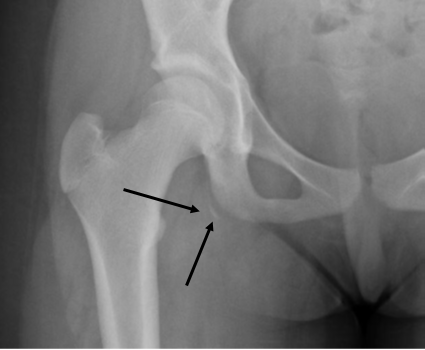

This patient sustained a hamstring avulsion. Diagnosis of such injuries is often missed or delayed, which results in complications such as sciatica, pain, weakness, stiffness, or even deformity.

- Hamstrings are comprised of three muscles: the biceps femoris, the semitendinosis, and the semimembranosis

- Origin of the hamstrings is the ischial tuberosity

- Avulsion injury at the myotendinous junction causes a small sliver of bone to be separated, which visible on the radiograph.